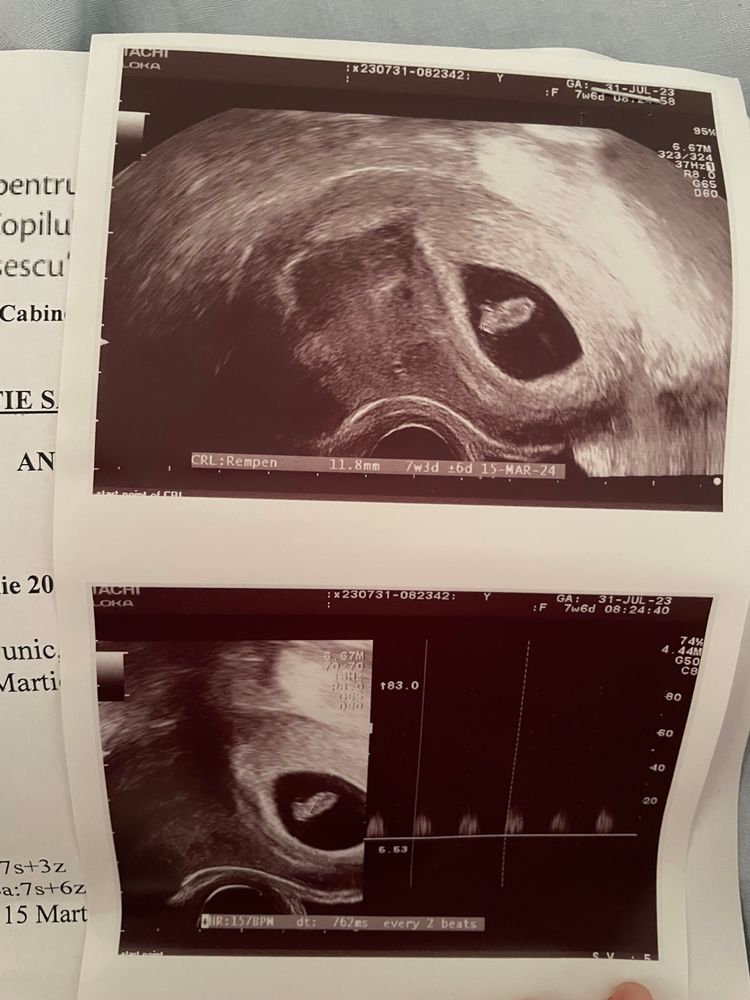

Кто расшифрует показатели по скринингу и пол малыша?🙈 Была сегодня на скрининге 🥹 срок по узи и месячным день в день. Пол сказала узистка даже смотреть не будет, как я не просила, сказала она мне терпеть 🥲 отправлю замерчики😁 правда они на укр языке. Посмотрите знающим глазом 😁🫂 и может кто по фото поймёт пол малыша, интерес берет своё

Добрый день, если есть узи на 7-8 неделе, то можно посмотреть по тесту Рамзи, на этом скрининге нужно смотреть под каким углом находится половой бугорок.

Настенька, ну по этому узи у вас девочка) Так как если фото узи перевернуть, то эмбрион будет слева, а слева по тесту Рамзи закреплены девочки, у меня совпало. Единственное у меня полукруг был вверху, а у вас на фото внизу, не знаю, зависит ли от него расположение эмбриона или нет.